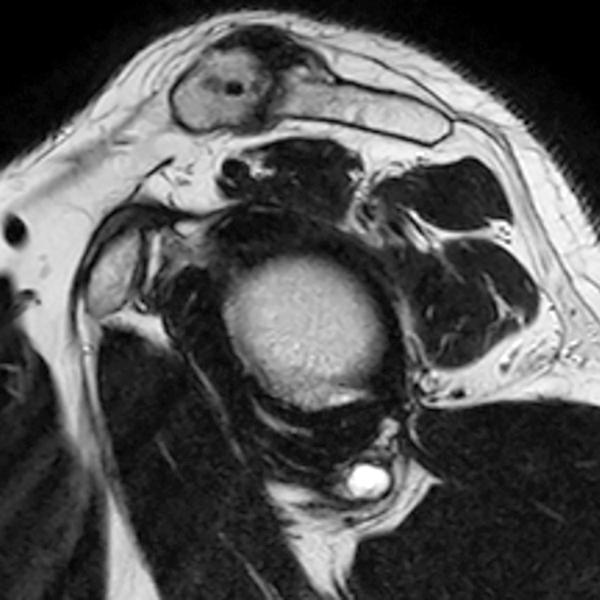

Shoulder Cysts Mri

From radsource.us

Shoulder Cysts Radsource Back Shoulder Cyst It's important to pay attention to the lump on your shoulder and its associated symptoms to determine if you should seek medical attention. Lumps on the shoulder are often associated with traumatic events, however, causes can also be inflammatory, cancerous, or environmental. They can develop anywhere around the shoulder but are the most common type of cyst on back of. Back Shoulder Cyst.